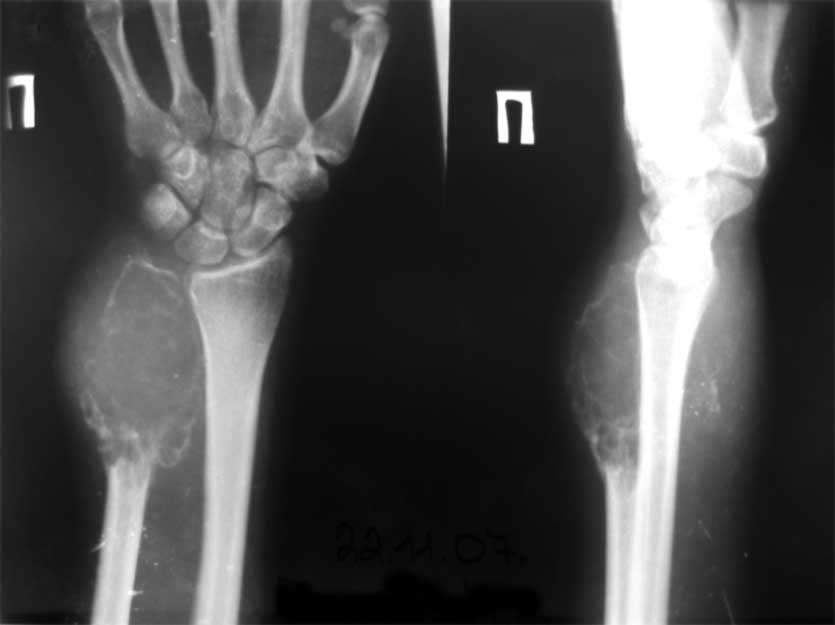

Привет, Максим! рентгенологически явные признаки малигнизации ГКО.

Летом 07 года пациентка 17 лет была прооперирована в детском отделении (рентгенологическая картина та же, гистология(от онкологов, открытая биопсия) - остеобластокластома литический вариант без признаков малигнизации.

Уважаемые коллеги, госпитализировали, наконец, эту пациентку, чему не очень рады, как клиническая, так и рентгенологическая картины изменились, кроме того Hb 76.Направил на повторную консультацию к онкологу. Остеобластеокластома может себя так вести?

Клинико-рентгенологически очень похоже на хондросаркому..... Хотя, конечно же, необходимо гистологическое заключение...

Плоховато она выглядит на снимках.

Уважаемые коллеги. По данным рентгенограммы опухоль больше похожа на злокачественную фиброзную гистиоцитому или телеангиоэктотический вариант остеогенной саркомы с поражением кожных покровов. По данным 6 отделения ЦИТО (Бурдыгин В.Н., А.В. Балберкин) и докторской диссертации А.Н. Махсона при поражении низкодифференцированной, т.е. высокозлокачественной опухолью кожных покровов или магистральных сосудисто-нервных структур органосохраняющие оперативные методы лечения не показаны, т.к. имеются отдаленные не диагностируемые метастазы. Показано комбинированное оперативное лечение по принципам неоадъювантной ПХТ.

Может при озлокачествлении (литическая форма), но уж больно похоже на хондро SA.